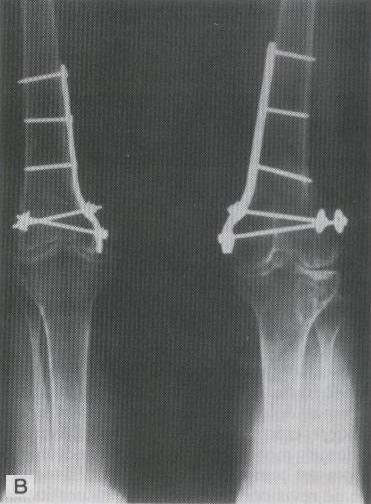

FIJACION CON IMPLANTE PARA FRACTURA DEL EXTREMO DISTAL DEL FEMUR BILATERAL